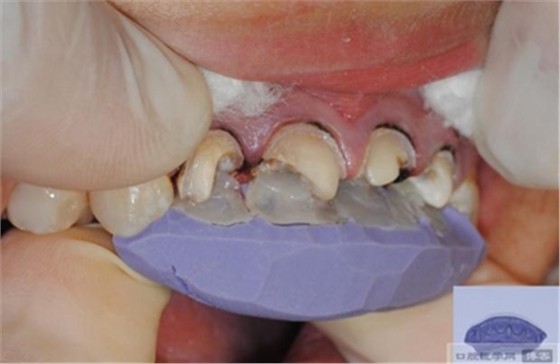

選擇合適的完成鉆制備根管,

通常深入到根管的1/2至2/3處

在使用根管纖維樁時(shí)根管預(yù)備的深度應(yīng)該是多少呢?

在回答這個(gè)問(wèn)題前,首先應(yīng)該了解根管內(nèi)的粘接狀況。最佳的粘接效果發(fā)生于根管的冠1/3和中1/3。由于根1/3的牙本質(zhì)小管往往不能充分敞開(kāi),此區(qū)域幾乎沒(méi)有粘接作用發(fā)生,所以,根管纖維樁放置的深度無(wú)需超過(guò)根中1/3。同樣重要的是,根管預(yù)備時(shí)鉆的速度不要過(guò)快,防止飛濺的牙膠粘在根管內(nèi)壁上。所以,根管壁的清理也很重要,以確保牙本質(zhì)小管充分開(kāi)放。Dr.Vanini使用噴砂和酸蝕來(lái)充分清理根管壁和窩洞。研究顯示,粘接劑的作用也很重要,粘接根管纖維樁要求使用滲透力強(qiáng)粘結(jié)作用好的粘接劑。

【纖維樁制作】

修整纖維樁長(zhǎng)度

取出纖維樁,按所需長(zhǎng)度裁截纖維樁 在有水條件下 用切割砂片或車針截取纖維樁,切勿使用鉗子,剪刀或鑷子以免破壞樁的結(jié)構(gòu)

將樹(shù)脂粘接劑均勻涂抹在根管、牙體的粘接面以及纖維樁表面,涂抹兩遍

粘接

將調(diào)好的樹(shù)脂水門汀用口內(nèi)注射頭送入根管

將纖維樁表面涂滿調(diào)好的樹(shù)脂水門汀,安放在根管內(nèi)就位,保持壓力10秒